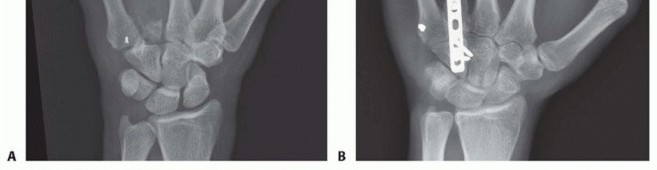

Standard radiographic imaging forms the cornerstone of diagnostic evaluation, requiring, at minimum, a dedicated posteroanterior (PA), a true lateral, and a pronated oblique view of the injured hand. The PA view is excellent for assessing coronal plane angulation and transverse displacement, though it notoriously underestimates sagittal plane deformity. The true lateral view is critical for quantifying apex-dorsal angulation, though overlapping metacarpal shadows can complicate interpretation. The pronated oblique view often provides the clearest visualization of the fracture profile and the degree of comminution.

When standard radiographs are equivocal, or when dealing with complex intra-articular fractures and suspected CMC fracture-dislocations, advanced cross-sectional imaging is mandatory. High-resolution Computed Tomography (CT) with 3D reconstructions provides unparalleled detail of articular step-offs, occult comminution, and the precise spatial orientation of fracture fragments. This information is invaluable for determining the feasibility of lag screw fixation versus the necessity of bridge plating. Furthermore, obtaining radiographs of the uninjured, contralateral hand serves as a vital anatomical template, allowing the surgeon to accurately gauge the patient's native metacarpal length and intrinsic diaphyseal curvature.

Open Reduction and Internal Fixation (ORIF) Approaches

When closed reduction fails, or for complex, comminuted, or multiple metacarpal fractures, Open Reduction and Internal Fixation (ORIF) is mandated. A dorsal longitudinal or slightly gently curved incision is made centered over the fractured metacarpal. Careful subcutaneous dissection is performed to identify and meticulously retract the dorsal sensory nerve branches using vessel loops. The extensor apparatus is exposed. Depending on the fracture location, the extensor tendon can be retracted laterally, or the extensor mechanism can be split longitudinally (e.g., splitting the EDC tendon) to access the dorsal periosteum.

Periosteal elevation must be judicious and strictly limited to the footprint required for plate application. Circumferential stripping of the periosteum is a catastrophic error that devascularizes the bone fragments and invites nonunion. The fracture site is gently debrided of hematoma and interposed soft tissue. Anatomical reduction is achieved using specialized reduction forceps, taking immense care to avoid crushing fragile cortical edges. Provisional fixation is maintained with fine (0.035-inch or 0.045-inch) K-wires.

Plate and Screw Fixation Execution

The application of hardware must adhere to strict biomechanical principles. For long oblique fractures, interfragmentary lag screws are the most biomechanically efficient method of achieving absolute stability. The technique requires drilling a gliding hole (e.g., 2.0mm or 2.4mm) in the near cortex, followed by a smaller thread hole (e.g., 1.5mm or 1.8mm) in the far cortex, utilizing a specialized drill guide. The near cortex is countersunk to prevent the screw head from acting as a stress riser or irritating the overlying tendon. As the screw is tightened, the fracture fragments are dynamically compressed together.

When a dorsal plate is required, it must be meticulously contoured to match the natural dorsal convexity of the metacarpal to prevent secondary displacement during screw insertion. For transverse fractures, the plate is applied in compression mode using eccentrically placed screws. For comminuted fractures, the plate functions as a bridge, bypassing the zone of comminution to maintain length and alignment without disturbing the fracture hematoma. Locking screws are utilized in osteoporotic bone or very short distal segments to prevent hardware pullout.

Following definitive fixation, a rigorous fluoroscopic check is performed in multiple planes to confirm anatomical reduction, appropriate hardware placement, and crucially, to ensure no screws are penetrating the volar cortex excessively, which could tether the underlying flexor tendons. The tourniquet is deflated, meticulous hemostasis is achieved, and the extensor mechanism is meticulously repaired with fine absorbable sutures. The skin is closed without tension, and a bulky, well-padded dressing is applied, splinting the hand in the intrinsic-plus position.